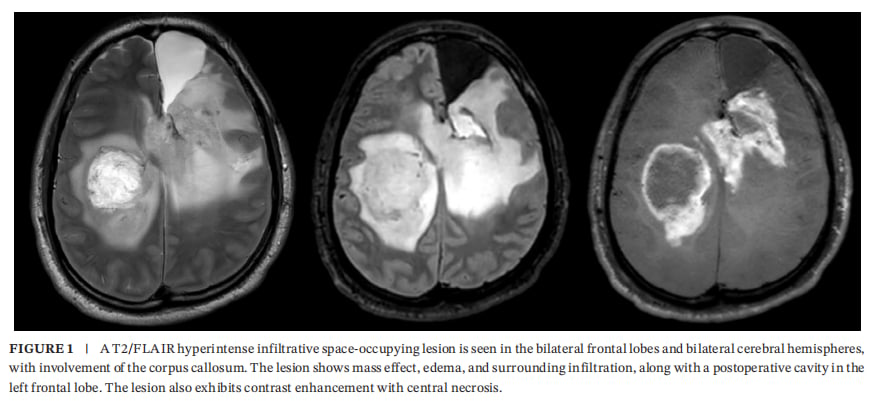

患者男,31岁,以两次癫痫发作伴意识丧失就诊。MRI显示双侧额叶、双侧大脑半球存在T2/FLAIR高信号浸润性占位病变,并累及胼胝体;病灶伴水肿、周边浸润,且可见强化与中心坏死。功能磁共振提示病灶邻近运动功能区,为手术风险评估提供依据。

双侧额叶及双侧大脑半球可见T2/FLAIR高信号浸润性占位性病变,累及胼胝体